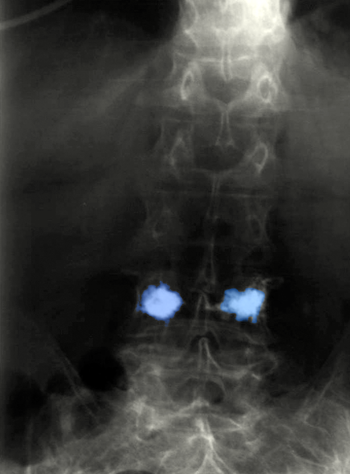

Σπονδυλοπλαστική οσφυϊκού σπονδύλου. |